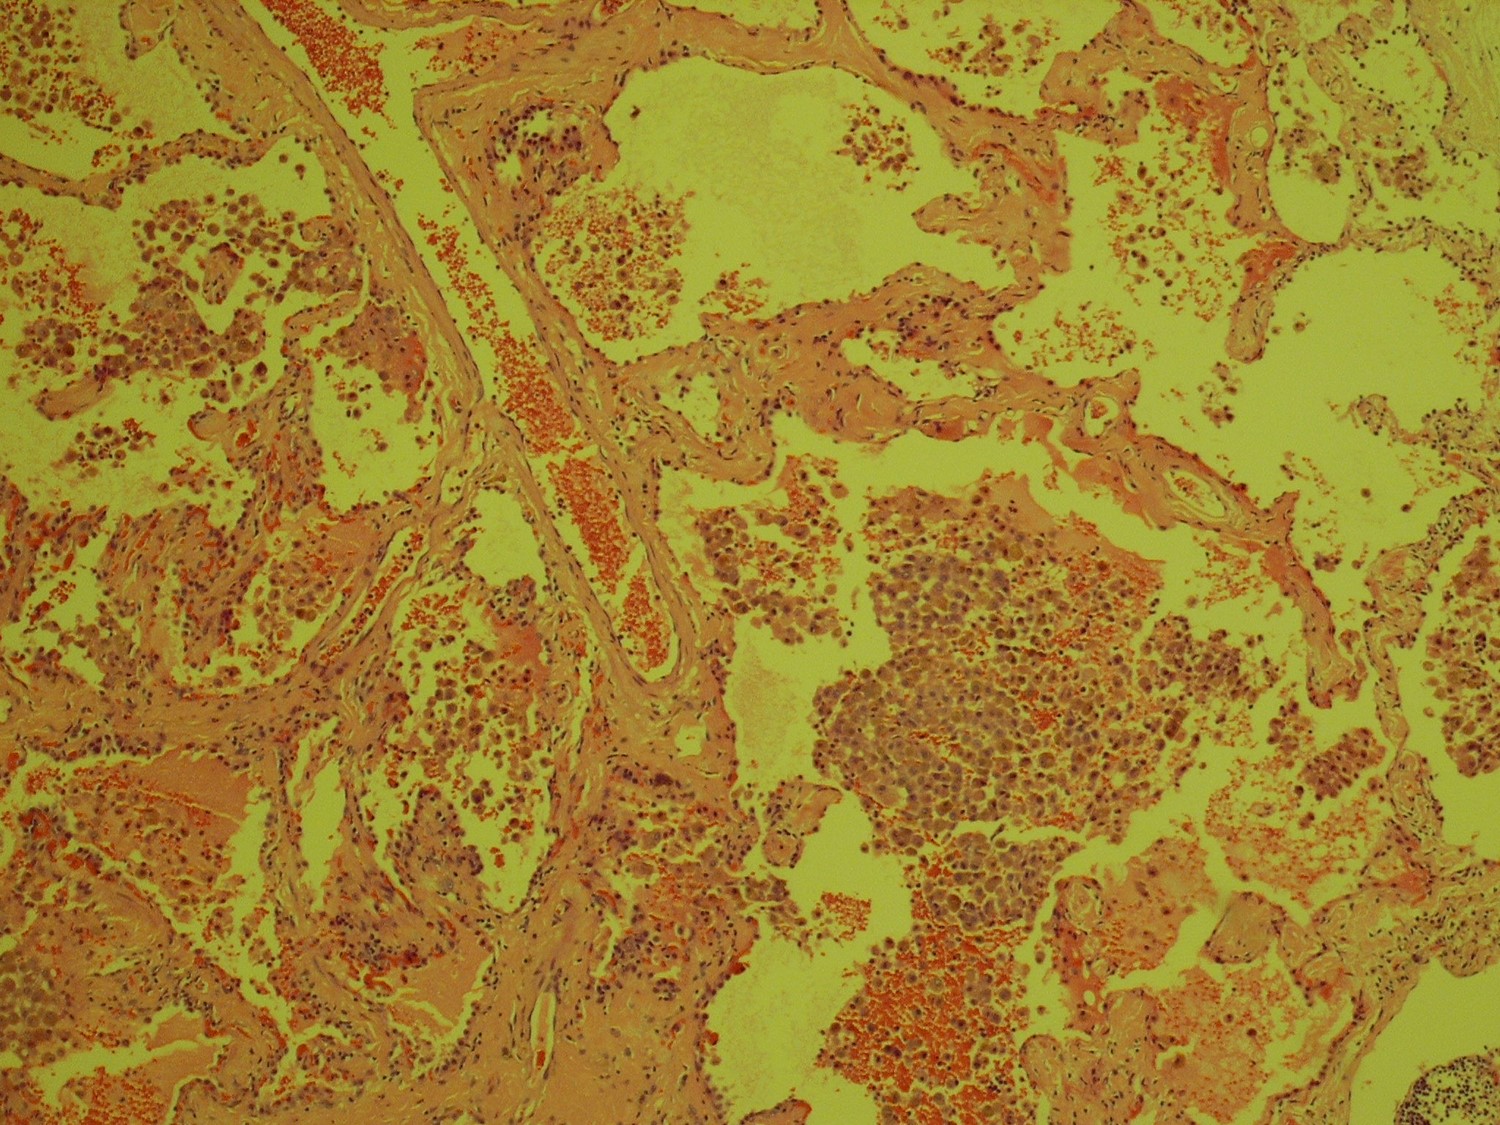

| The answer is “C”, Fibrotic NSIP with DIP- like reaction For most patients who undergo VATS biopsies for interstitial lung disease, the fundamental question is, “Is this IPF?” For the pathologist, that translates to “Is this UIP or could it be something else?” This case lacks the geographic and temporal heterogeneity of interstitial fibrosis characteristic of UIP. There is no honeycomb change and there are no fibroblastic foci. It is not UIP/IPF. Instead, there is uniform, bland fibrous thickening of alveolar septa in specimens from all three lobes, characteristic of fibrotic non-specific interstitial pneumonitis (NSIP). The abundant intra-alveolar pigmented macrophages raise the possible diagnosis of desquamative interstitial pneumonitis (DIP), a condition highly related to smoking. In fact, cases of DIP can have areas of NSIP-like interstitial fibrosis, but these are usually focal and more scar like. In cases in which the septal fibrosis is uniform and widespread, the diagnosis of NSIP with DIP-like reaction is preferred. The final two images are a bonus, an incidentally discovered pulmonary hamartoma from the right lower lobe wedge biopsy. Katzenstein, AL, Katzenstein and Askin’s Surgical Pathology of Non-Neoplastic Lung Disease, Major Problems in Pathology (MPP 13), Fourth Edition. Saunders, 2006. Pp. 61-74. |